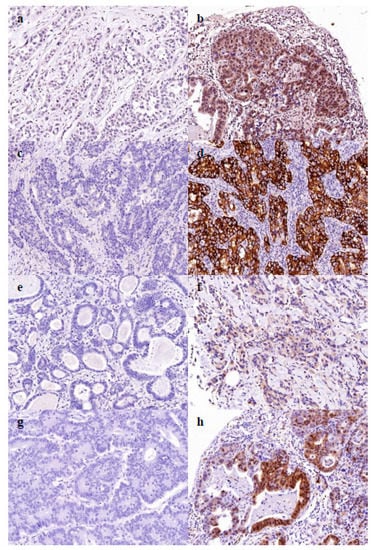

2.5. Cancer Dormancy Marker Expression

4.4. Expression of Cancer Dormancy Marker